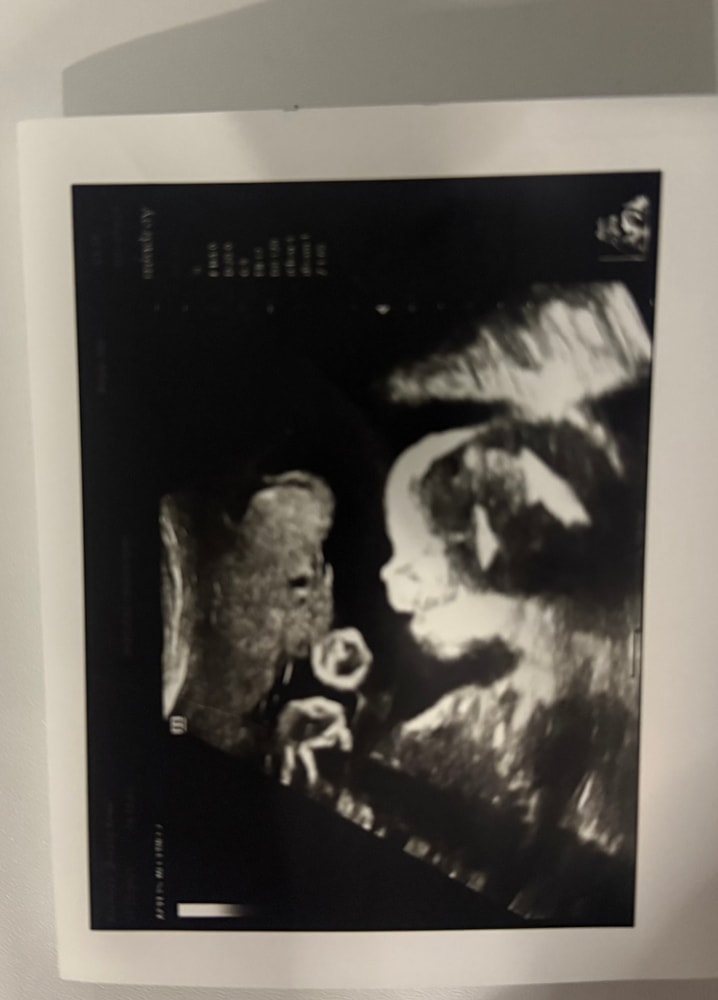

УЗИ на 27,2 неделе

УЗИ, КТГ, доплерВсем привет!🌸Сегодня ходила на внеплановое узи,по большей части ради своего интереса как там растет и развивается малыш.Сегодня еще такая пасмурная и сонная погода…поэтому сын на узи тоже лежит и зевает,особо не активничает😅мне запечатлели этот момент.Развиваемся мы согласно сроку,весим уже 1110 гр